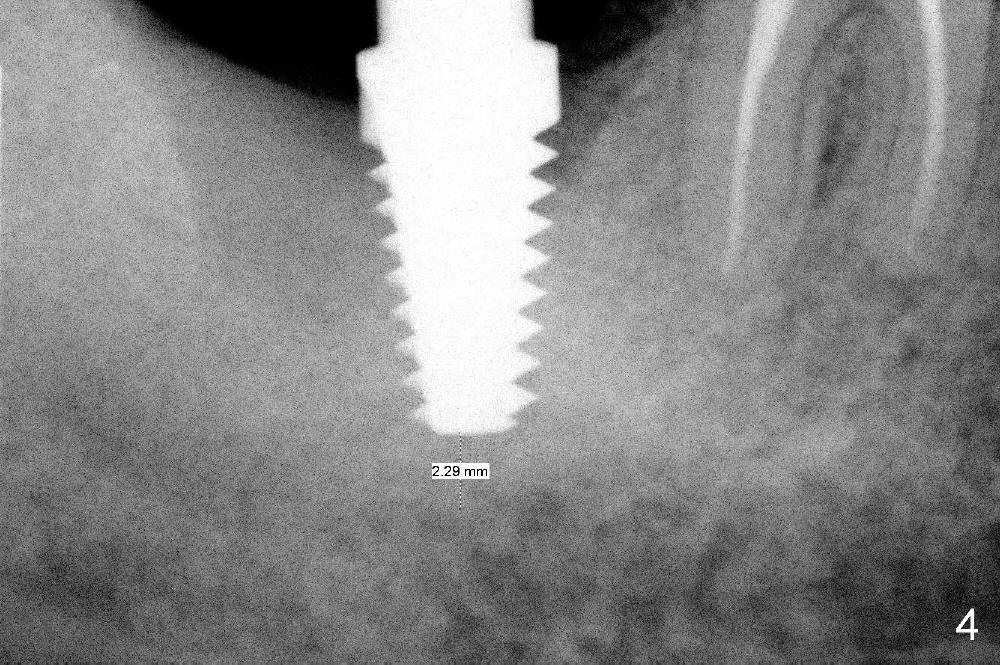

No. First at all, CT should be taken when 2D image does not show IAN. Fortunately, the surgery happens to be executed better than the plan. Clindamycin is used for socket soaking for 5 minutes. The initial osteotomy should be not exceeded 6 mm from the distal surface of the first molar (Fig.3: 5.92 mm). The 2 mm pilot drill (D) penetrates the mesial slope of the socket (red line) for 3-4 mm. There is 2.72 mm from IAN (yellow line: upper border of IAN canal). If the implant is placed along the long axis of the tooth, the initial osteotomy should start at the apex of the socket. The same pilot drill (black outline) penetrates the nascent bone for the same distance (3-4 mm) for primary stability, IAN may be invaded! The patient is a severe gagger. She manages to allow us to take this PA (Fig.3) and the next one (Fig.4 with 6x14 mm tap in place, primary stability having been achieved). To close the socket, a 7x14 mm implant is placed. Immediately postop PA is taken twice without success. The socket is closed with 2 sutures and heals around the implant 8 days postop (Fig.5,6). PA is taken 2 months postop (Fig.7). The implant is not placed as deep as planned. It is stable without paresthesia of the lower lip. An abutment is placed (Fig.8: A) nearly 3.5 months postop.